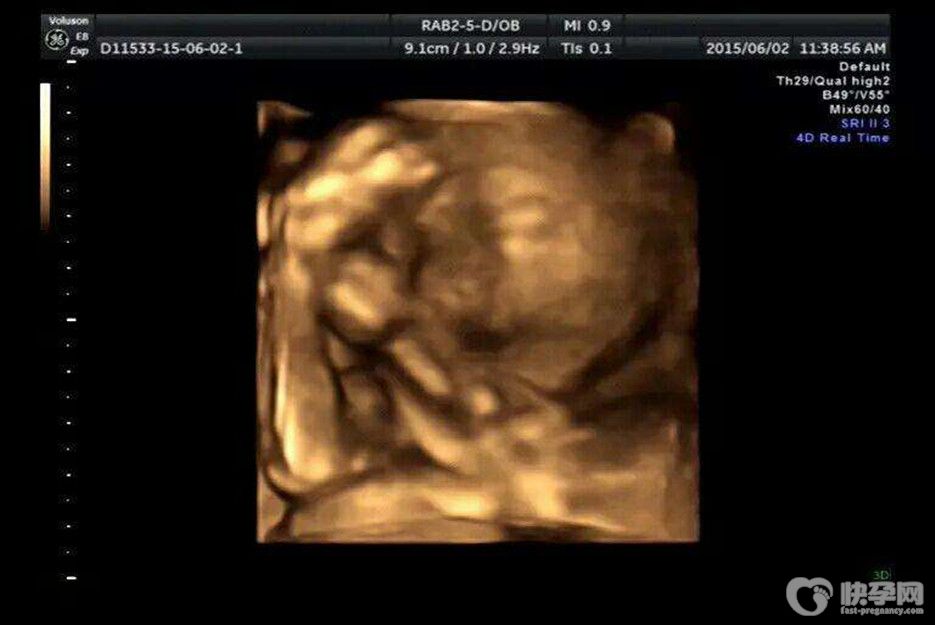

NT哪三个亮点能看出来是男孩女孩? 网传通过NT检查可以看到胎儿的性别特征和生殖器特点,腿间亮点和白线就是重要判断依据,如果看到胎儿双腿间有三个亮点的话可大致判断为..

随着科学技术的不断发展,孕检在早期就能揭开胎儿性别的神秘面纱,其中NT指的是颈背部透明带厚度。而在孕检过程中,有三个亮点可以帮助准父母区分胎儿的性别。那么孕检中NT..

很多准妈妈怀孕后好奇怀的是女孩还是男孩?听说NT上有3个亮点的,多数是男宝宝。这种说法是真的吗?生殖专家说:这种说法不靠谱。网传:根据nt结果看胎儿性别的方法双腿间..

很多准爸爸准妈妈不是重男轻女,而只是单纯的想知道是男孩还是女孩,以便后续准备宝宝衣服。但我们通过民间办法的话也需要在五六个月肚子稍微隆起才敢根据形态猜测男女。那..